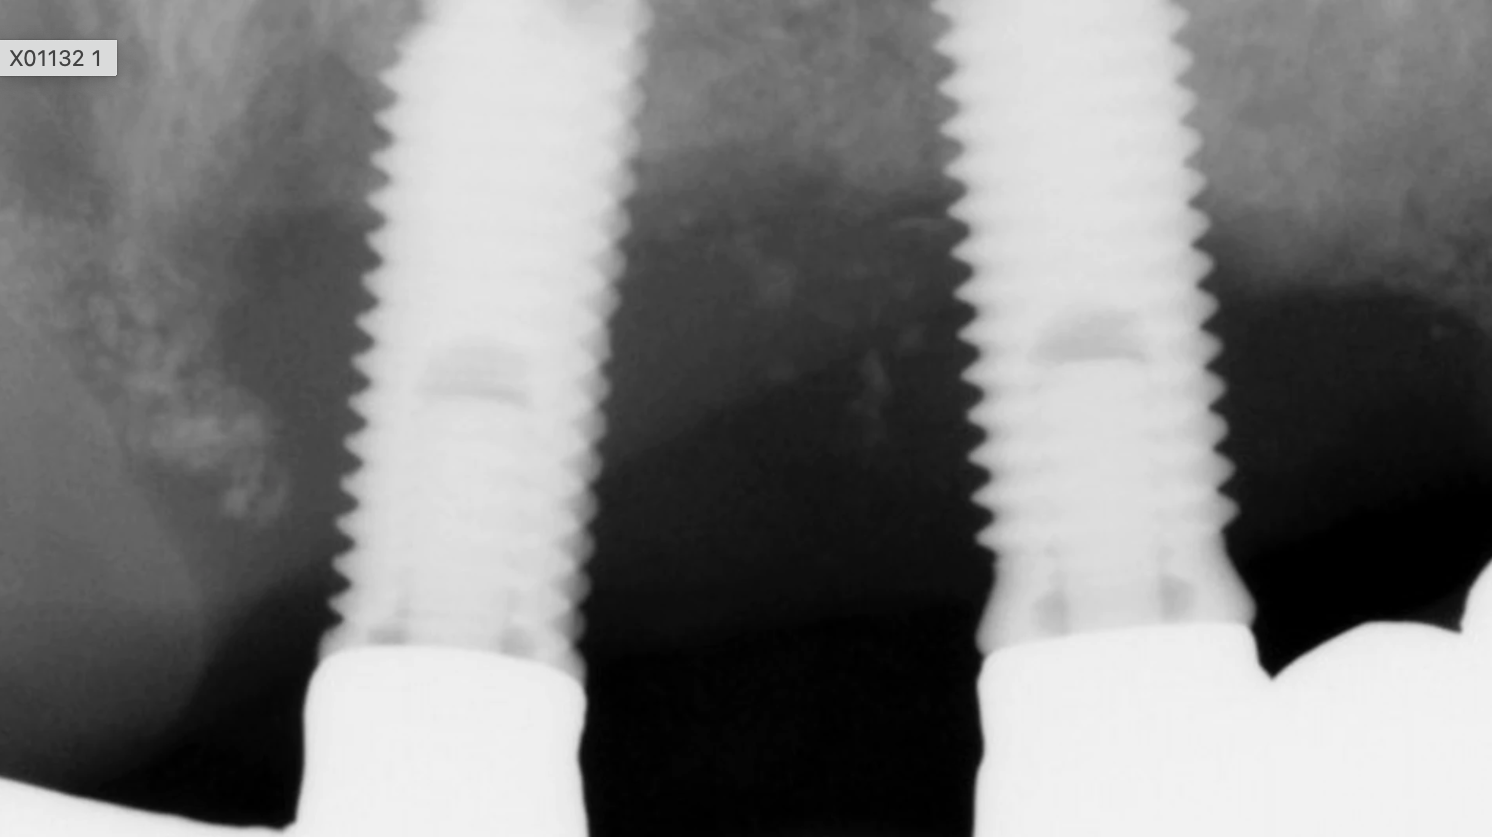

Not everyone who wants an implant is eligible. There are several factors to consider when selecting the ideal implant patient. It should be someone with good overall health, good oral health, adequate bone levels to support the implant, and healthy gum tissue free of periodontal disease. The success rate for those who smoke or take certain medications is lower for various reasons. A patient’s health history will serve as a foundation for determining what treatment to do.

It’s all about that bone

Are you doing a bone graft or placing a membrane? This is often necessary when there isn’t enough bone to support a future implant. There are many options available and each circumstance is different, and your doctor will decide which system will work best in each situation. Clear as mud, right? Exactly!